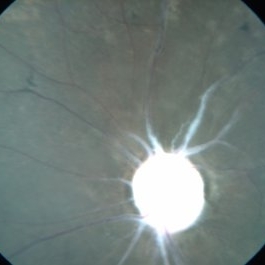

Optic Nerve Head Avulsion

Sep 15 2014 by Mehul A Shah

A 30-year-old male presented with loss of vision following blunt trauma.

Photographer: Drashti Netralaya,Dahod

Imaging device: Zeiss ff450

Condition/keywords: optic nerve head avulsion